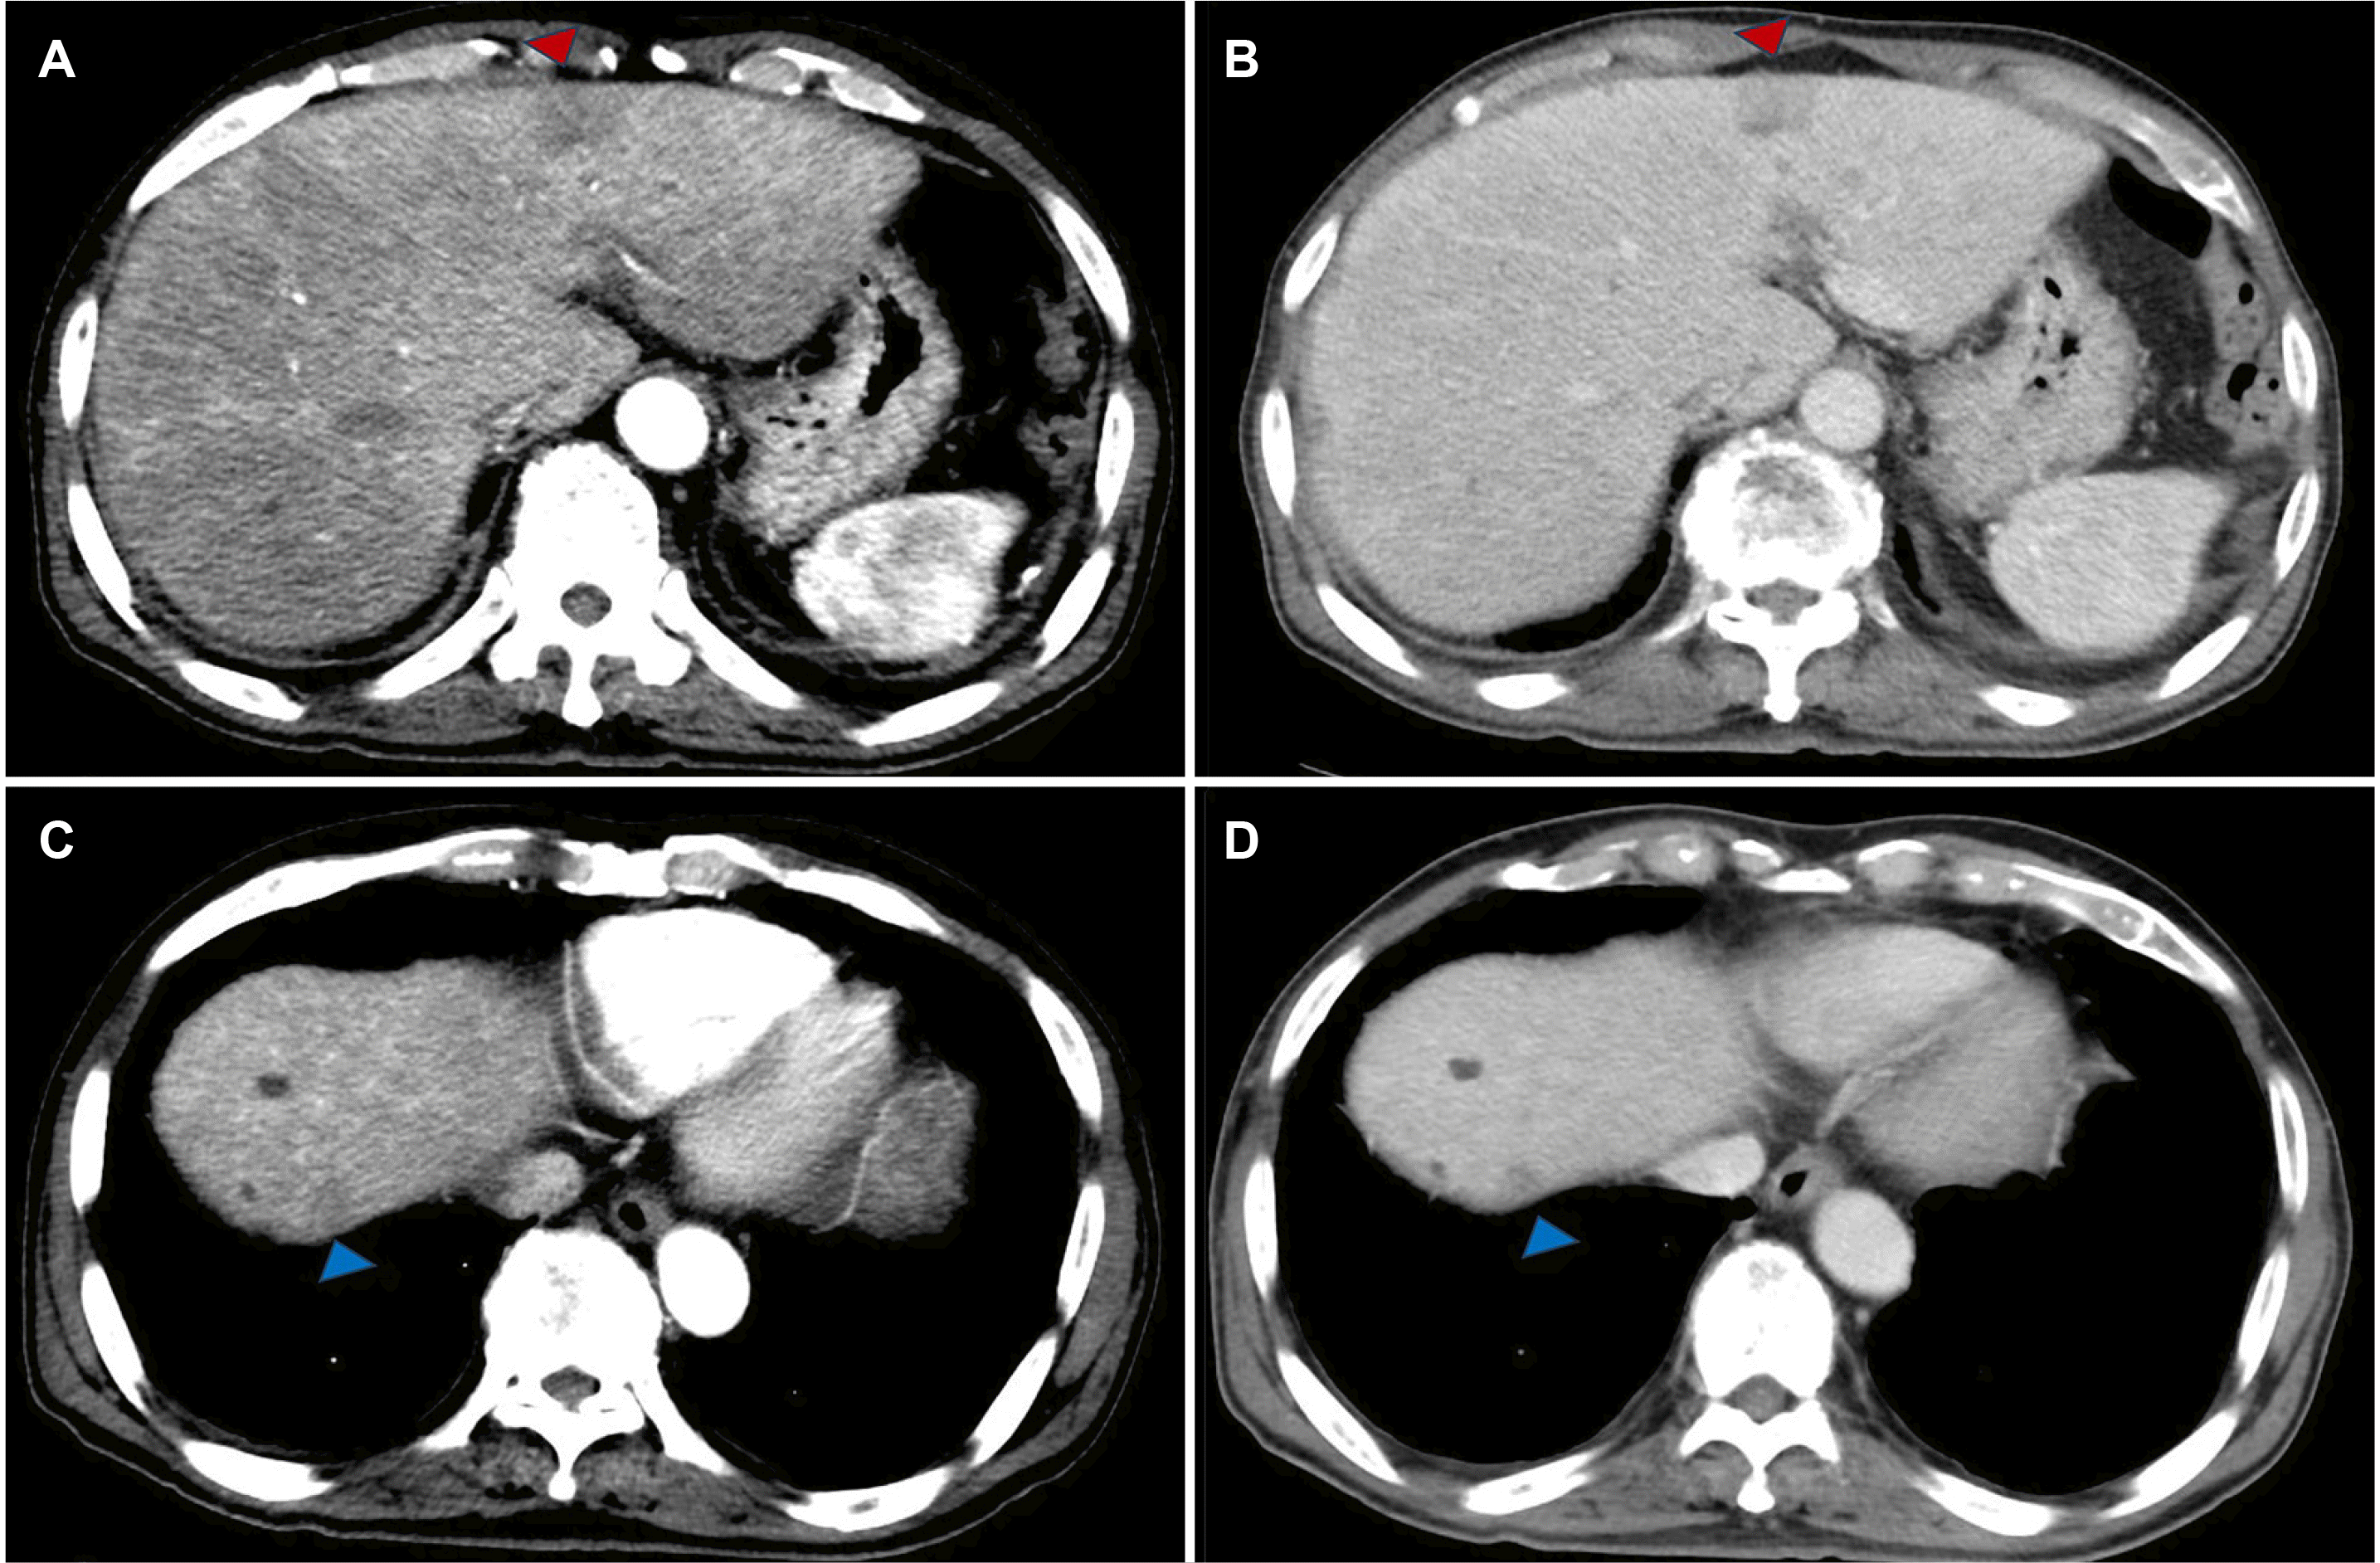

Upon examination, the patient's vital signs were found to be stable, with a body temperature of 36℃, a pulse rate of 102 beats/min, a respiratory rate of 18/min, and a blood pressure of 111/79 mmHg. Liver function tests demonstrated a cholestatic pattern with the following results: Aspartate aminotransferase level of 132 U/L, alanine transaminase level of 36 U/L, alkaline phosphatase (ALP) level of 501 U/L, and gamma-glutamyl transpeptidase level of 522 U/L. Abdominal CT demonstrated a 2.5 cm-sized heterogeneous nodule within S3/4 of the liver, exhibiting diffusion restriction but unclear margins prior to contrast enhancement. Furthermore, a 1 cm-sized low-density lesion was identified in S8 of the liver (Fig. 1).

These were initially diagnosed as benign lesions, suspected to be inflammatory liver abscesses. The patient was treated with an empiric regimen of piperacillin-tazobactam for one week. However, the patient's symptoms persisted. Follow-up imaging did not demonstrate any improvement (Fig. 2).

Fig. 1

Axial contrast-enhanced computed tomography: (A) In the arterial phase, a heterogeneous hypodense hepatic nodule 2.5 cm in size is observed in S3/4 of the liver (red arrowhead). (B) In the portal phase, an ill-defined hypodense hepatic nodule is seen. (C) In the arterial phase, a heterogeneous hypodense hepatic nodule 1 cm in size is seen in S8 of the liver (blue arrowhead). (D) In the portal phase, an ill-defined hypodense hepatic nodule is seen (blue arrowhead).